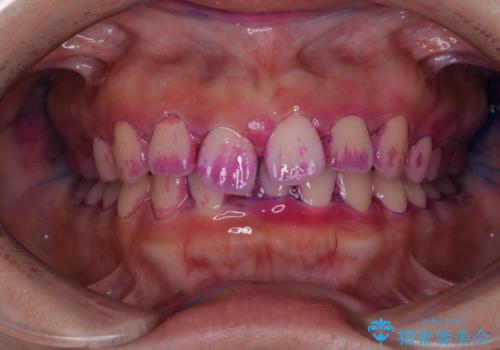

2カ月で全体的に着色(PMTC)

- クリーニングをしてほしいとのことで来院されました。

PMTC30分コースを行いました。

インビザラインの矯正中の方でアタッチメントが歯に付いているため、2ヶ月で着色やプラークが付いてきてしまいました。ホームケアや飲食の仕方により個人差はありますが、基本的には汚れが普段よりもつきやすいです。